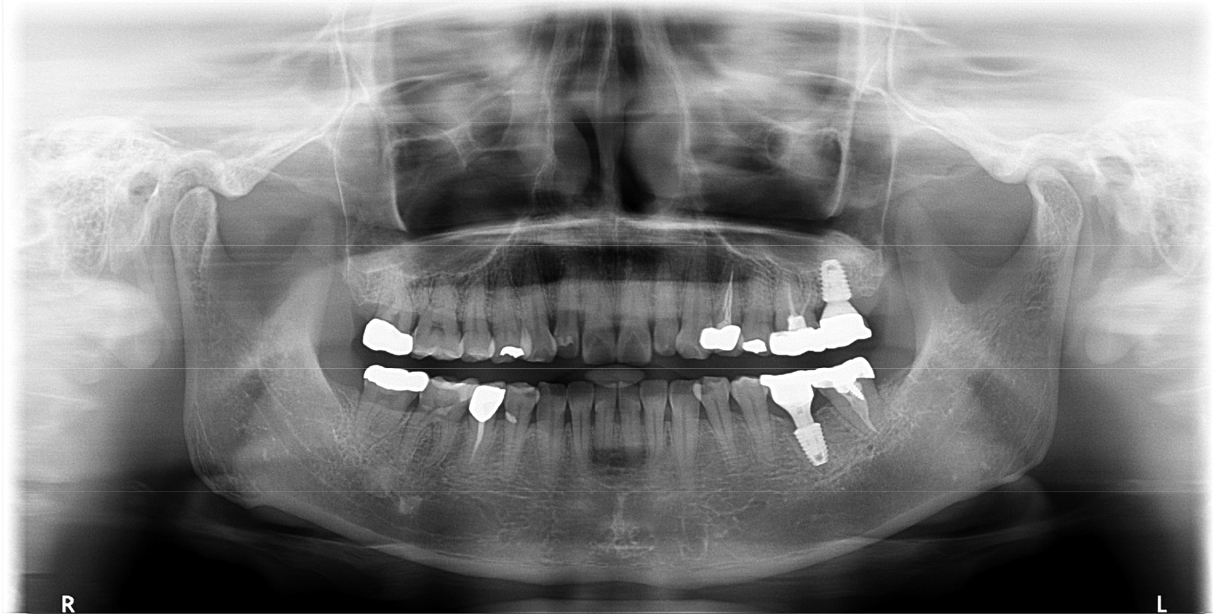

After 4 months of the first surgery, the ISQ value was 71, showing favorable stability, the prosthesis was placed consecutively, and healing progress was observed (Fig. 8A, 8B). After 5 months, the final prosthesis was completed (Fig. 9A, 9B). Supported treatment was initiated and radiographs were taken after 6 months (Figs. 10, 11, 12). In the radiograph analysis, the alveolar bone surrounding the dental implant was stable, with ossified bone verified. In a 6-month interval, the supported treatment was conducted in April 2022, showing no signs of peri-implant gingivitis or bone resorption (Figs. 13 and 14).